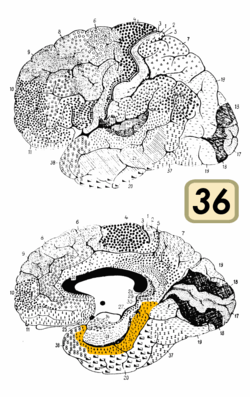

Brodmann area 36

Ectorhinal area 36 is a subdivision of the cytoarchitecturally defined temporal region of cerebral cortex. With its medial boundary corresponding approximately to the rhinal sulcus it is located primarily in the fusiform gyrus. Cytoarchitecturally it is bounded laterally and caudally by the inferior temporal area 20, medially by the perirhinal area 35 and rostrally by the temporopolar area 38 (H) (Brodmann-1909).

Together with Brodmann area 35, it comprises the perirhinal cortex.